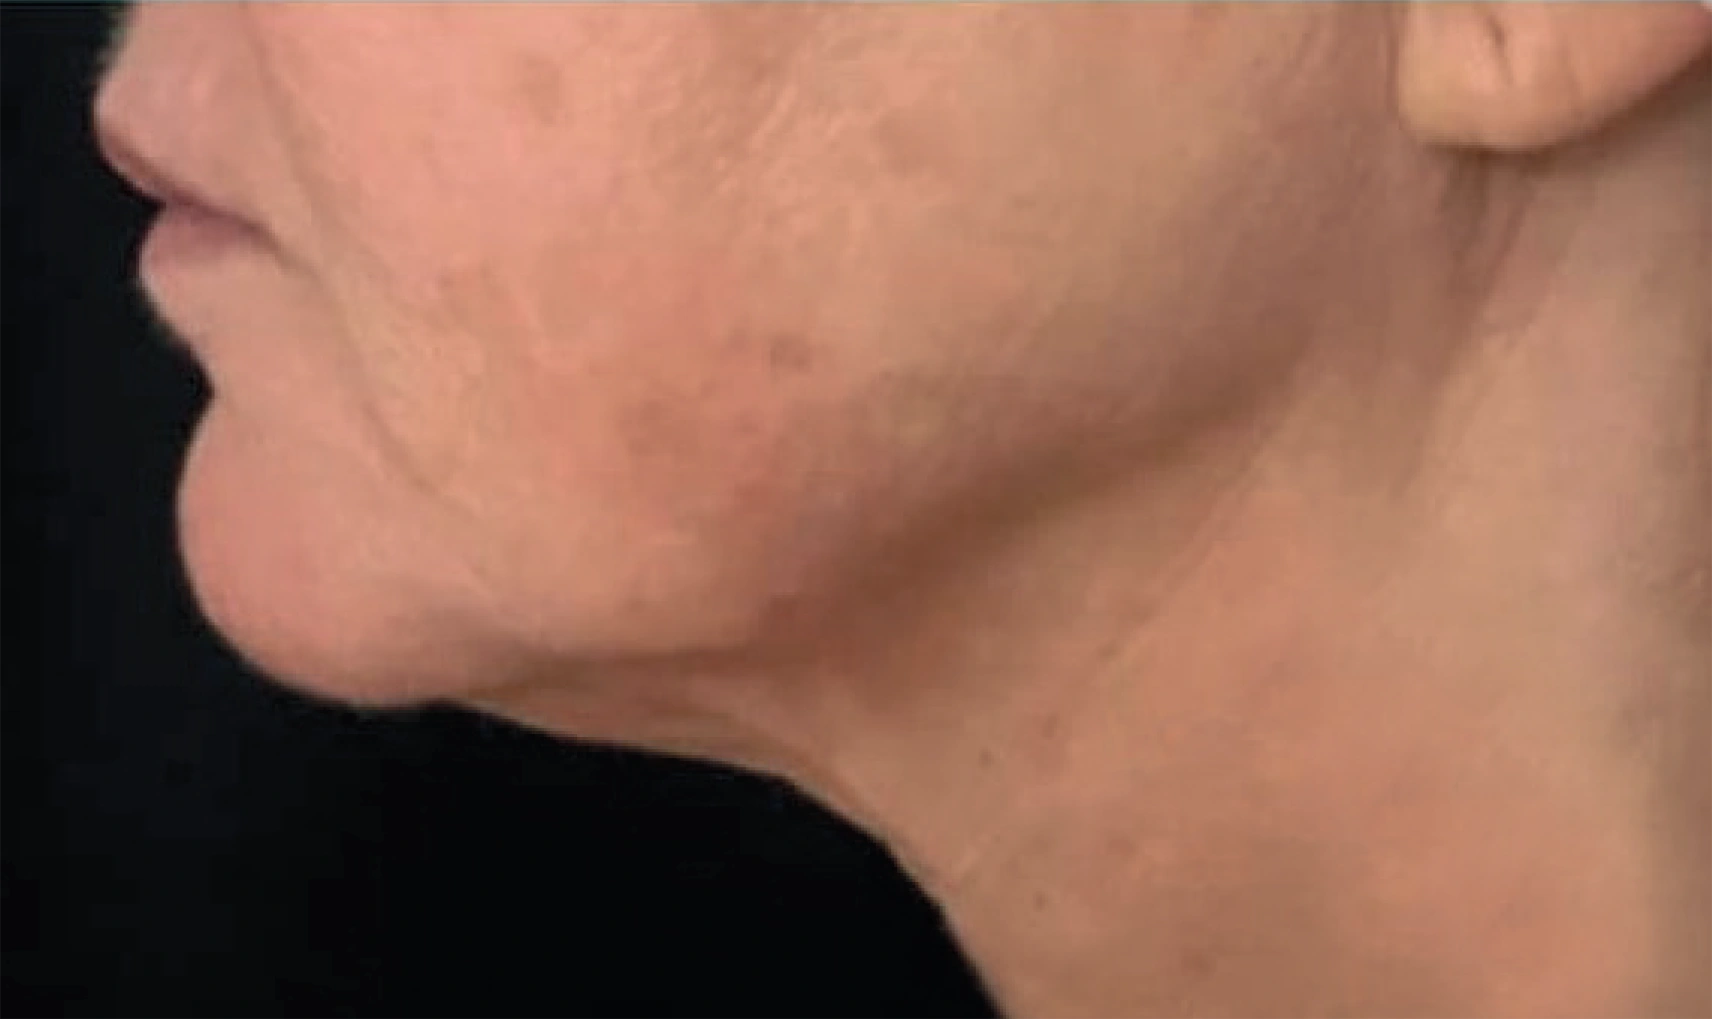

ENDOLIFT® ist eine minimalinvasive Laseranwendung mit dem LASEmaR® 1500, die auf eine Verbesserung der Hautqualität und eine definiertere Gesichtskontur abzielt – ohne sichtbare äußere Verletzungen. Das Verfahren wird in Bereichen angewendet, in denen eine beginnende Hauterschlaffung erkennbar ist, zum Beispiel im Gesicht, am Kinn, am Hals oder im Unterlidbereich.

Bei ENDOLIFT® Verfahren werden sehr feine, flexible Einwegfasern knapp unter der Haut im oberflächlichen Unterhautgewebe platziert. Dafür reicht in der Regel ein kleiner Einstich aus. Je nach Areal und Empfindlichkeit kann eine leichte lokale Betäubung eingesetzt werden, der Eingriff wird jedoch von vielen Patientinnen und Patienten als gut tolerierbar beschrieben.

Nach der Behandlung kann es vorübergehend zu leichten Rötungen, Schwellungen oder Verfärbungen kommen. Diese Reaktionen sind individuell unterschiedlich und klingen in der Regel selbstständig ab. Die meisten Personen können ihre normalen Aktivitäten zeitnah wieder aufnehmen.

Während einzelne Effekte bereits früh sichtbar sein können, entwickelt sich das Ergebnis typischerweise über einen längeren Zeitraum weiter. Das Verfahren kann körpereigene Prozesse, wie eine Verbesserung der Hautstruktur, unterstützen. Wie stark und wie lange diese Effekte anhalten, hängt von individuellen Faktoren wie Hautbeschaffenheit, Stoffwechsel und Lebensstil ab.

Viele Patientinnen und Patienten berichten unmittelbar nach der Behandlung von einem ersten Straffungsgefühl. Dieser frühe Effekt kann sich in den folgenden Wochen verändern. Im weiteren Verlauf können körpereigene Regenerationsprozesse, wie die Neubildung von Kollagen, zu einer graduellen Verbesserung der Hautstruktur beitragen.

Neben der Straffung in der Tiefe kann sich auch das Hautbild an der Oberfläche im Verlauf harmonisieren. Wie lange die Ergebnisse sichtbar bleiben, hängt von individuellen Faktoren wie Hautbeschaffenheit, Stoffwechsel und Lebensstil ab. Falls gewünscht, lassen sich Wiederholungsbehandlungen flexibel planen.